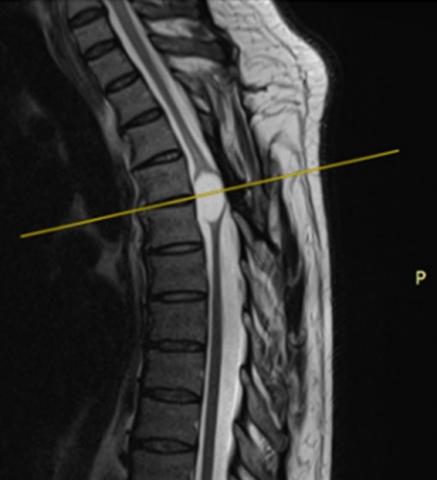

Vertebral hydatidosis: case report

JOHN VARGAS U, OSMAR ORDINOLA C, EDUARDO LAOS P, ALFONSO BASURCO C.